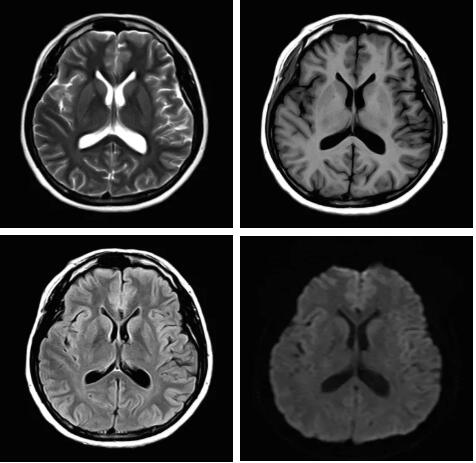

圖:Pure射頻成像鏈的優(yōu)化和改進(jìn)使信噪比提升

從成像源頭的磁體采用鍍膜新磁體高密度薄層鍍膜貼合技術(shù),獲得更好的磁場均勻度,奠定磁共振成像基礎(chǔ);采用3D RSCE微雕梯度精準(zhǔn)控制頻率和相位,輸出理想波形,實(shí)現(xiàn)渦流的“0”殘余,還原最真實(shí)的圖像信息;射頻接收端通過計(jì)算機(jī)人工智能對(duì)信號(hào)抗干擾處理,把信號(hào)放大并去除梯度、磁場等對(duì)信號(hào)干擾,再經(jīng)過二次人工智能信號(hào)識(shí)別,去除噪聲污染獲得純凈的信號(hào);通過Pure射頻成像鏈的優(yōu)化和改進(jìn)使信噪比提升40%,這是磁共振領(lǐng)域革命性的顛覆和改變。